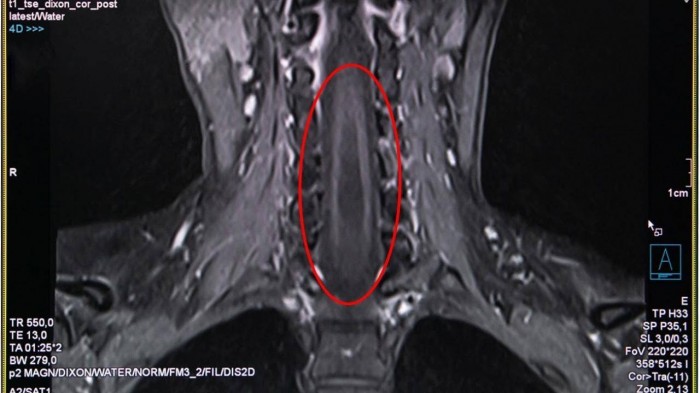

Chính vì vậy, tôi đã chỉ định cho bệnh nhân chụp cộng hưởng từ MRI cột sống và tuỷ sống để đánh giá tình trạng tổn thương và để loại trừ các bệnh lý khác có liên quan”, Bs Hải Yến cho hay.

Kết quả chụp MRI tủy sống, cho thấy trong đoạn tủy sống của chị hình thành một hốc rỗng chứa các dịch, các dịch này tích lại thành các khoang và nang hốc đây là biểu hiện của căn bệnh rỗng tủy.

Theo các chuyên gia về thần kinh cột sống, bệnh rỗng tủy là do ở trong đoạn tủy sống hình thành một hốc rỗng ở trung tâm của chất xám chứa dịch não tủy. Dịch não tủy tích lại hình thành các khoang hoặc nang hốc phát triển lớn dần và gây huỷ hoại tuỷ, chèn ép dây thần kinh, khiến bệnh có biểu hiện là những rối loạn vận động, rối loạn cảm giác và dinh dưỡng.